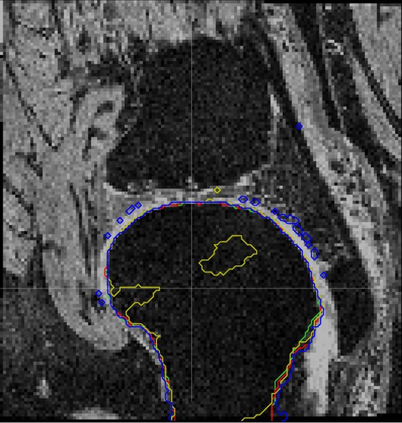

Direct automatic segmentation of objects from 3D medical imaging, such as magnetic resonance (MR) imaging, is challenging as it often involves accurately identifying a number of individual objects with complex geometries within a large volume under investigation. To address these challenges, most deep learning approaches typically enhance their learning capability by substantially increasing the complexity or the number of trainable parameters within their models. Consequently, these models generally require long inference time on standard workstations operating clinical MR systems and are restricted to high-performance computing hardware due to their large memory requirement. Further, to fit 3D dataset through these large models using limited computer memory, trade-off techniques such as patch-wise training are often used which sacrifice the fine-scale geometric information from input images which could be clinically significant for diagnostic purposes. To address these challenges, we present a compact convolutional neural network with a shallow memory footprint to efficiently reduce the number of model parameters required for state-of-art performance. This is critical for practical employment as most clinical environments only have low-end hardware with limited computing power and memory. The proposed network can maintain data integrity by directly processing large full-size 3D input volumes with no patches required and significantly reduces the computational time required for both training and inference. We also propose a novel loss function with extra shape constraint to improve the accuracy for imbalanced classes in 3D MR images.